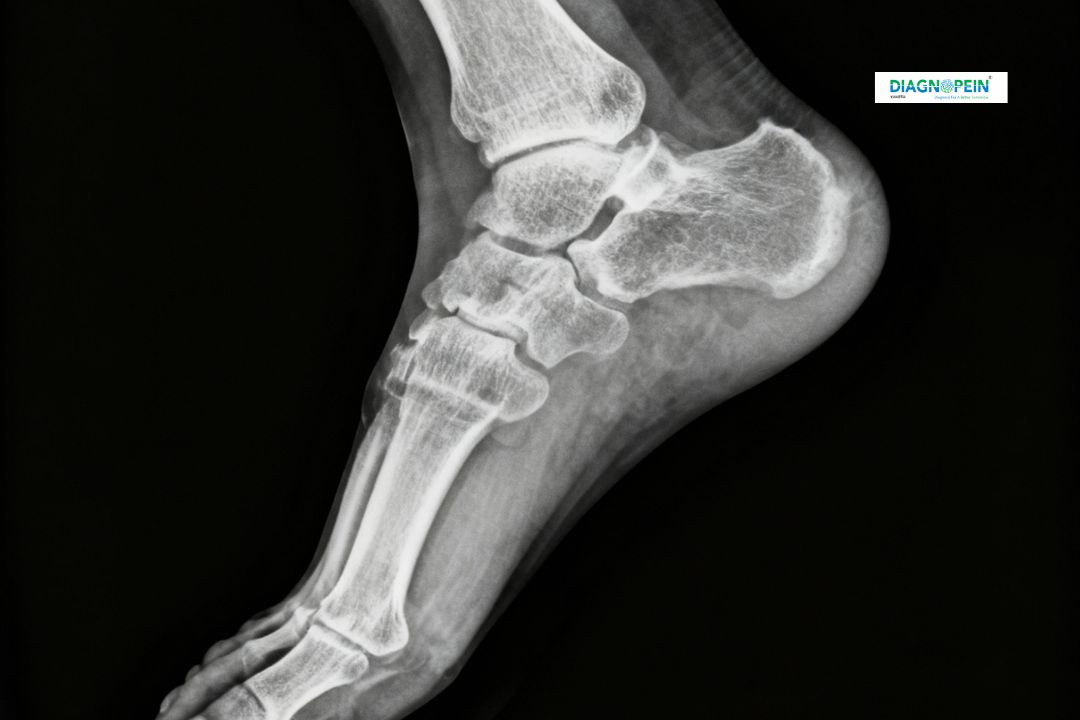

The X-Ray Right Oblique View is a specialized imaging technique used to capture detailed images of bones, joints, and soft tissues when a standard front or side view is insufficient. This view helps provide a clear understanding of overlapping bone structures by angling the body or limb at an oblique position.

Accuracy in diagnosis depends on viewing the bones from multiple angles. The X-Ray Right Oblique View fills the gap when frontal (AP) and lateral views are not adequate. It helps clinicians gain additional insight into complex fractures, joint deformities, and internal misalignments.

Parameters typically captured in the Right Oblique View include the bone alignment, cortical continuity, joint space, and surrounding soft-tissue structure. If necessary, additional views may be suggested for comprehensive evaluation.